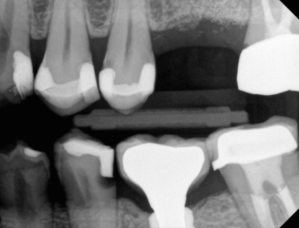

#20 DO

#19 DO and #18 MO